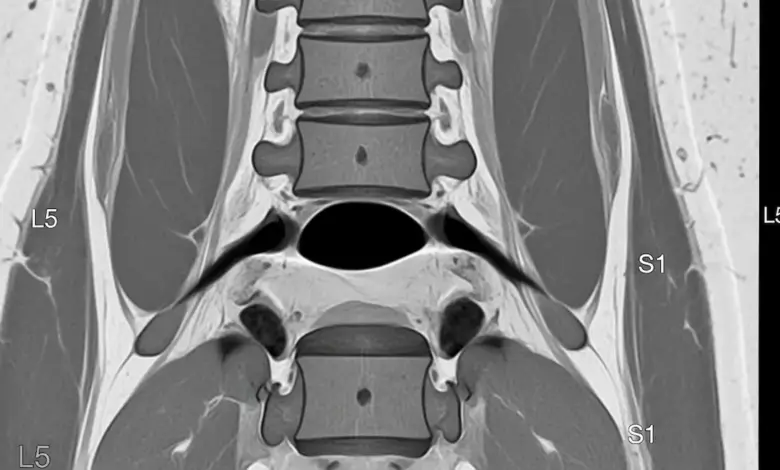

Discopatia degenerativa L5 S1 com protusão discal: entenda!

A expressão discopatia degenerativa L5 S1 com protusão discal descreve o desgaste do disco entre a última vértebra lombar e o sacro, somado a um abaulamento do disco que pode irritar raízes nervosas.

- Ressonância magnética: método de eleição para visualizar a degeneração e protusão.

A intensidade da dor nem sempre corresponde ao tamanho da protusão. O laudo precisa ser interpretado junto do exame clínico e do contexto funcional do paciente.